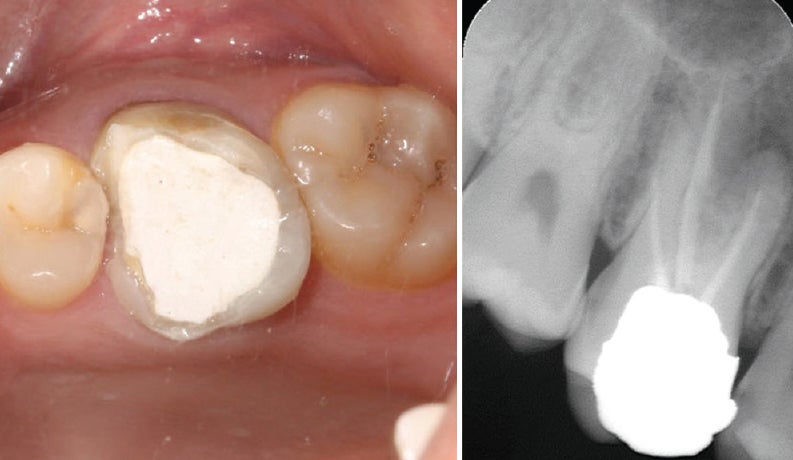

- 진단 및 엑스레이: 감염 범위 확인

- 신경 접근: 충전물 제거 후 내부 접근

- 영구 충전 및 보철: 최종 봉합 후 크라운 등 보철